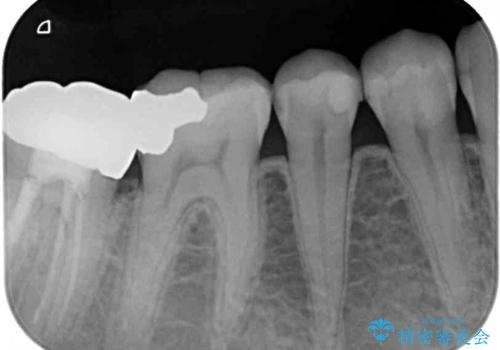

- 右上下の奥歯がむし歯でしみたり痛んだりするとのことで来院された患者様です。

下顎の奥歯は強い痛みを感じており、既に歯髄に不可逆的な炎症が起きていると診断されたため、根管治療の後にセラミッククラウンにて補綴治療を行うこととしました。

上顎の奥歯は最近銀歯による治療を行ったとのことでしたが、適合が不十分であり隙間からしみていたため、適合の良いゴールドインレーにて修復治療を行うこととしました。

下顎のむし歯は歯肉の中にまで及んでいたため、一部歯槽骨を削除し、歯肉縁上に健全歯質が位置するよう外科処置を併用しました。